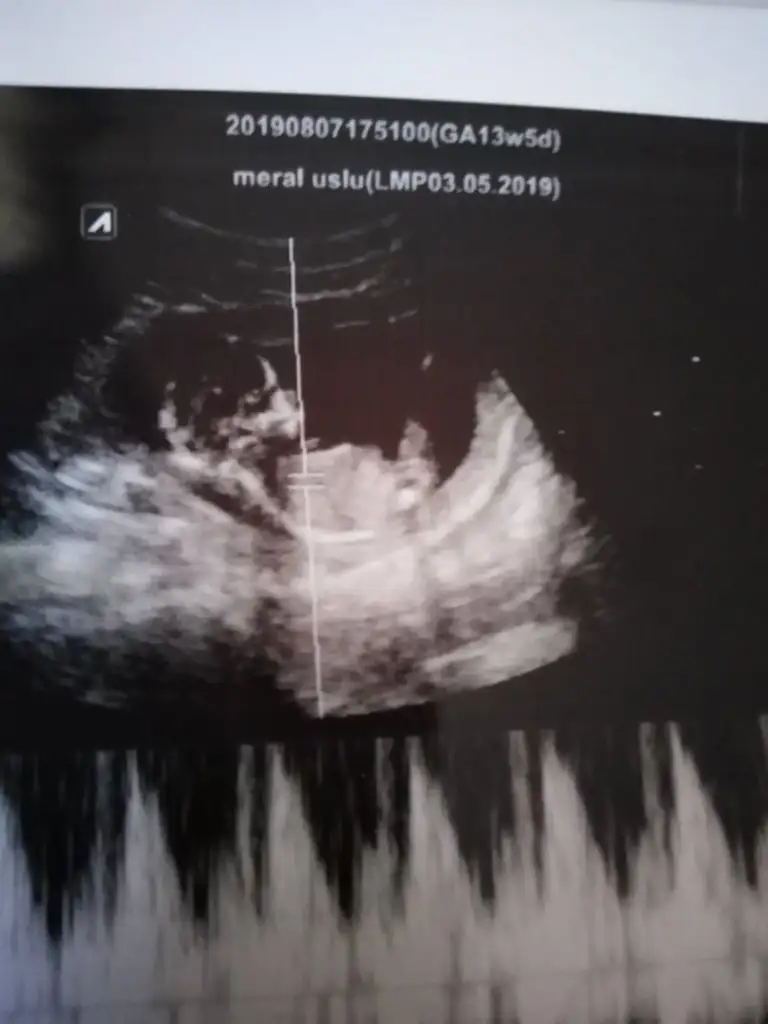

Kızdiyorum 13+5 da nub olmaz kafa sekli kız 11 yada 12 olmalı nub içincinsiyet nedir bakar mısınız

11 yada 12 hafta olmalı nub için kafa şekli kız gibiBizde tahmin alabilir miyiz 13+2

Teşekkür ederim yorumun için insan merak ediyor işte11 yada 12 hafta olmalı nub için kafa şekli kız gibi

Saglıkla gelsin paşacan tahminim tuttuTam dik degil ama ben tahminimi Erkek gibi yorumluyorum

Kaç haftalık 11 yada 12 olmalı sanki erkek gibiIkra meyra Dr bi tahmin yürüttü ama sizce belli mi cinsiyeti bu seferki görüntü de Eki Görüntüle 2297314